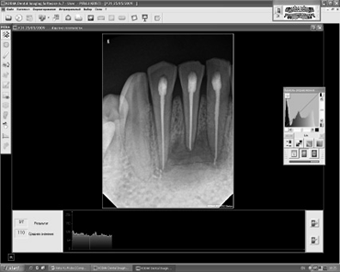

Пациентка Л. 20 лет, обратилась в клинику челюстно-лицевой хирургии б-цы “Мурацан” 17.03.2009 г. с жалобами на припухание мягких тка-ней в области подбордка и болезненность нижних фронтальных зубов. Отмечала травму, полученную в области подбородка в детсве. При осмотре -внешне асимметрия лица за счет припухлости мягких тканей в области подбородка, кожа над припухлостью слабо гиперемирована. Со стороны полости рта- отек и гиперемия слизистой в области переходной складки нижних фронтальных зубов. Фронтальные зубы интактны, перкуссия болезнена. Рентгенологическое исследование на RVG Kodak 6100 радиовизиогра- фе – показал дефект кости с четкими контурами под корнями 31.41.42 зубов, размерами 19x15, со средней плотностью кости 74УЕСЦ (условных единиц серого цвета): max-98 УЕСЦ, тт-53УЕСЦ (рис.За). После клинико-рентгенологического обследования был по-ставлен диагноз - травматическая радикулярная ки-ста подбородочного отдела нижней челюсти.

14.04.2009г. под местным обезболиванием проведена депульпация зубов, апексы которых находились в зоне кисты и операция - цистэктомия с заполнением костного дефекта по вышеописанной методике. Послеоперационный период протекал гладко, швы удалялись на 7-е сутки после оперции. При контрольном осмотре через месяц после операции- слизистая розового цвета, отечности мягких тканей не наблюдалось. При RVG денситометрии через 1мес после операции среднее значение плотности кости составляло 110 УЕСЦ: с max-132 УЕСЦ, min-97 УЕСЦ (рис.3Б). На 3-м же мес наблюдалось полное восстановление дефекта, с образованием органоти-пичной кости, с аналогичной изоплотностью с ма-теринской. Среднее значение плотности составляло 146 УЕСЦ: тах-172 УЕСЦ, тт-126 УЕСЦ.